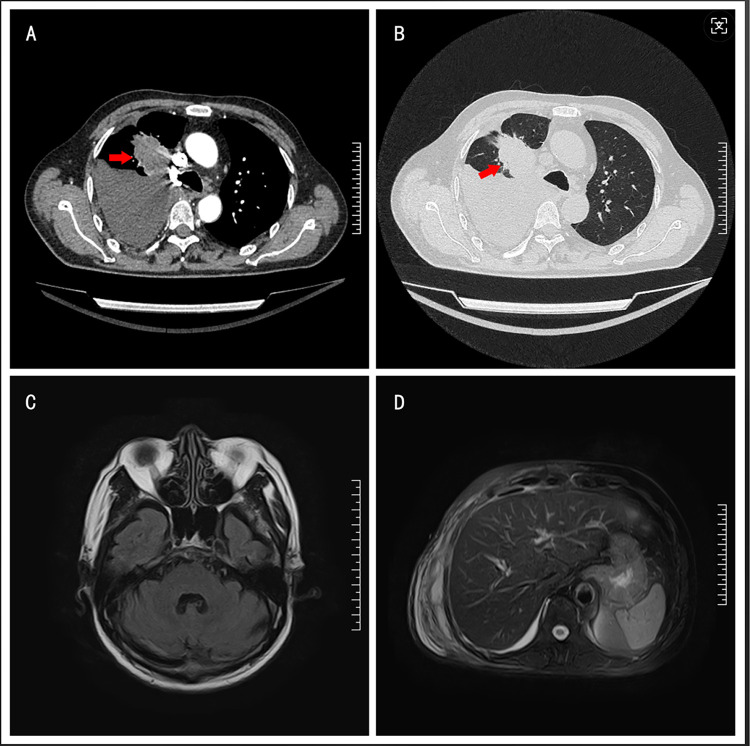

Case presentation: A 64-year-old male with a 30-pack-year smoking history presented with a 3-month history of progressive shortness of breath and chest tightness. Contrast-enhanced chest CT revealed a 5 cm spiculated mass in the right upper lobe, abutting the mediastinum, along with bronchial obstruction, right middle lobe atelectasis, and pleural effusion. A CT-guided transthoracic needle biopsy confirmed lung adenocarcinoma. Next-generation sequencing (NGS) identified a c.2573T>G (p.L858R) mutation in exon 21 of the EGFR gene and a c.35G>C (p.G12A) mutation in exon 2 of the KRAS gene. The patient started first-line therapy with osimertinib combined with pemetrexed/nedaplatin, resulting in a transient partial response, significant resolution of pleural effusion, and partial regression of the primary tumor. However, disease progression occurred within 6 months, marked by the appearance of a new cerebellar metastasis, confirmed by MRI. The patient continued osimertinib maintenance therapy and underwent stereotactic radiotherapy for the brain lesion. Despite initial stabilization, pulmonary progression was observed 11 months after the start of treatment. Due to declining performance status and personal preferences, the patient declined further treatment and was lost to follow-up.